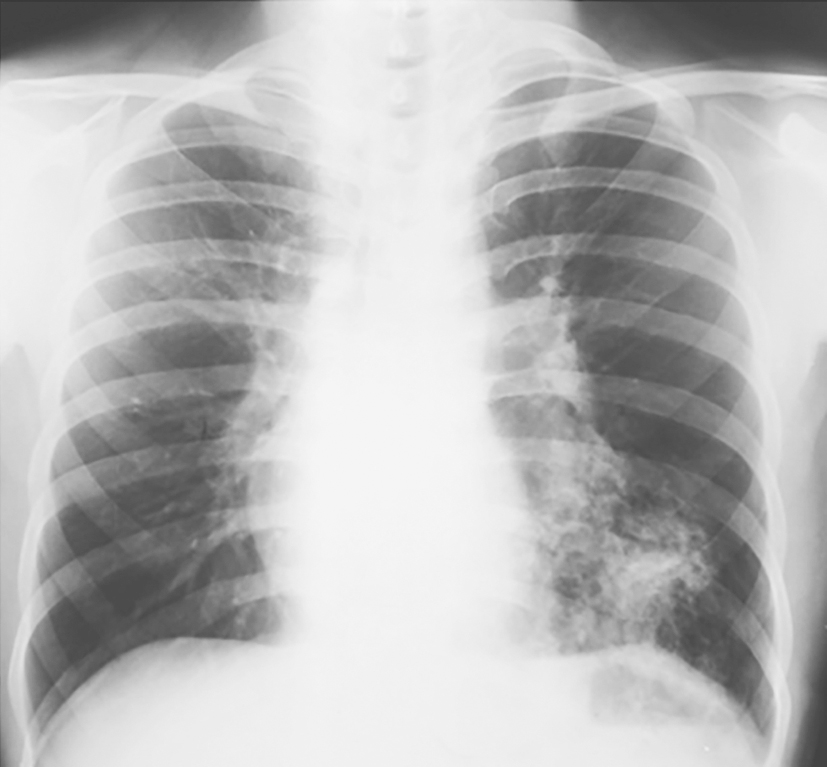

X线胸片(发病第10天):左下肺可见大片高密度影(图1)。

图1 发病第10天X线胸片表现